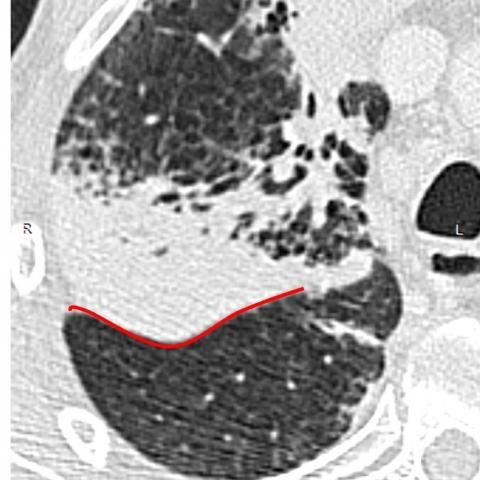

CT显示右上叶和中叶支气管充气征(图2和3)。上叶轻度小叶中心型肺气肿,下叶轻度间隔旁型肺气肿,下叶支气管壁增厚。纵隔淋巴结病变(图3)。无胸腔积液。

图2 因感染实质扩大,右上叶实变伴支气管征和右斜裂(红线)膨出